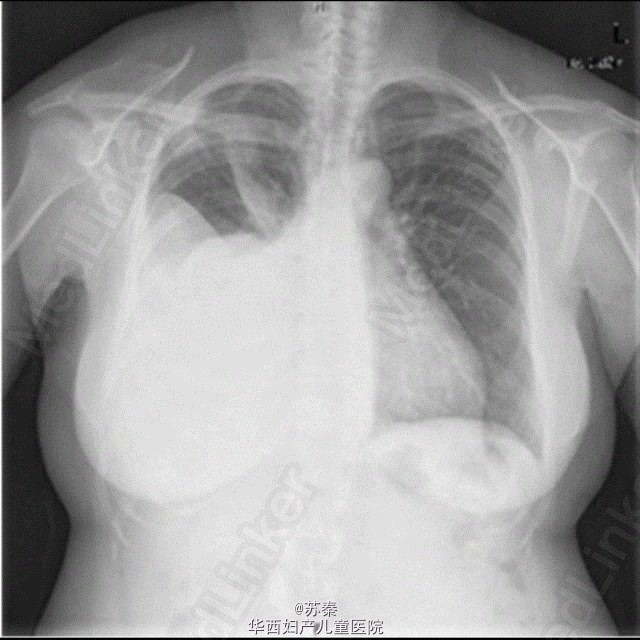

同期子宫内膜间质肉瘤与双侧卵巢腺癌

少见的同期子宫及卵巢癌 来自Olga Caramelo,A Case of Endometrial Stromal Sarcoma with Synchronous Bilateral Adenocarcinoma of Ovary,2012,Acta obstetricia et gynecologica Scandinavica